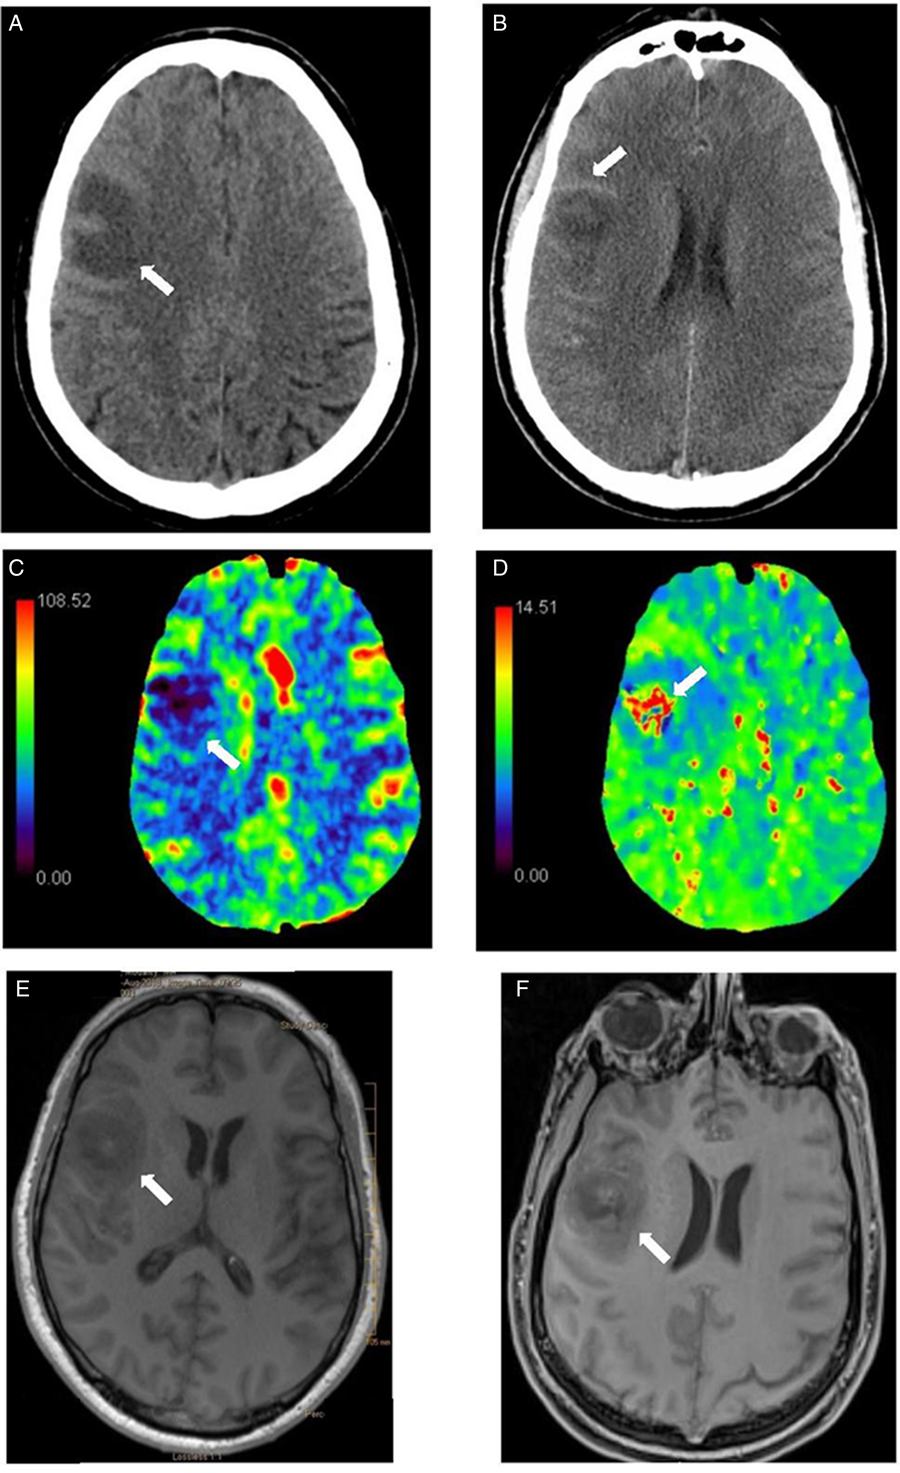

Head CT scan with and without contrast and CT perfusion at the time of admission (Figure 1(A–D)) showed a nonenhancing expansile subcortical hypodense lesion and low cerebral blood volume in the right frontal lobe suggestive of either a low-grade glioma or demyelination. Abscess was felt unlikely by the radiologist due to lack of ring enhancement. Sinuses and parameningeal structures were normal. He had mild leukocytosis (WBC 12.1), otherwise initial laboratories were unremarkable. Blood cultures were drawn. MRI brain, neurosurgical consultation, and lumbar puncture were planned. Six hours postadmission his level of consciousness (LOC) progressively declined, and he developed high fever (39.0°C), hypertension, tachycardia, and tachypnea. He was empirically started on intravenous vancomycin, ceftriaxone, ampicillin, and acyclovir. His LOC further deteriorated in the next hours such that he required intubation and transfer to ICU. MRI brain (Figure 1(E–F)) following clinical deterioration demonstrated diffuse leptomeningeal enhancement and right frontal opercular intra-axial mass suggestive of an atypical abscess. His antimicrobial regimen was then switched to vancomycin, ceftriaxone, and metronidazole. Lumbar puncture showed purulent cerebrospinal fluid (CSF) with 19,700 × 106/L WBC (90% neutrophils), high protein, and low glucose (12% of serum glucose) (Table 1). Subsequent blood and CSF cultures yielded S. pyogenes (group A streptococcus (GAS)). Further physical exam and investigations for potential source of GAS infection (e.g., transesophageal echocardiography for endocarditis) were unremarkable.

Figure 1: Head CT scan without (A) and with contrast (B): right frontal subcortical expansile hypodensity with subtle thin ring enhancement. (C-D) Head CT perfusion: decreased cerebral blood flow (CBF) (C) and cerebral blood volume (CBV) in the right frontal lesion with corresponding prolonged time-to-peak (TTP) (D). Differential considerations included low-grade glioma and demyelinating lesion given low cerebral blood volume. Note that abscess can have low CBV and therefore, can be difficult to be distinguished from glioma. Brain MRI without (E) and with Gadolinium enhancement-T1 cyberKnife (F) (performed 15 hours later): right frontal opercular intra-axial mass with surrounding vasogenic edema, peripheral rim of petechial hemorrhage and diffuse leptomeningeal enhancement. There was no restricted diffusion in the center of the lesion. The combination of findings was felt to be due to diffuse meningitis with cerebritis and evolving phlegmon/early abscess changes in the context of CNS bacterial infection. Given diffuse leptomeningeal enhancement post-Gd, neoplasm such as primary glioma was less likely. The appearance was not compatible with demyelinating disease.